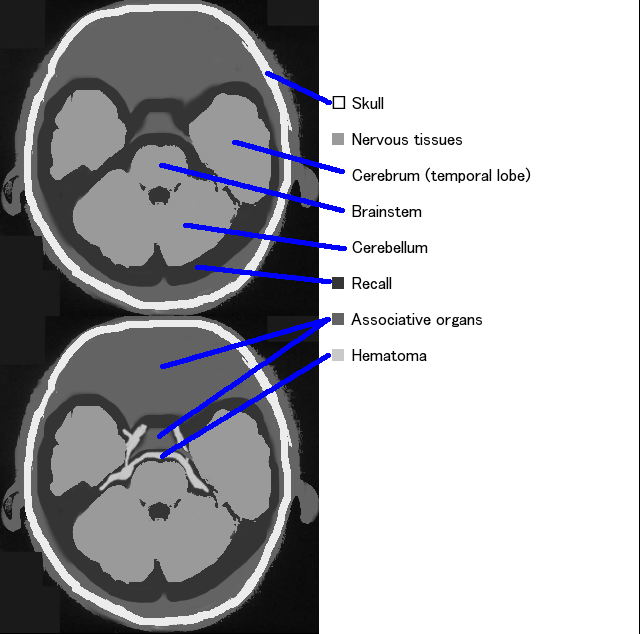

4. 1. 영상 검사

비조영 컴퓨터 단층 촬영술(CT) 촬영이 초기 진단에 가장 유용하며, 자기 공명 영상(MRI)은 시간이 경과했거나 혈종이 소량인 경우에 유용하다.[3] CT 스캔은 증상 발현 후 6시간 이내에 98.7%의 사례를 정확하게 식별할 정도로 높은 민감도를 보인다.[30] 며칠 후에는 MRI가 CT보다 더 민감하다.[2] 자기 공명 혈관 조영법(MRA)도 동시에 촬영할 수 있다는 장점이 있다.

두부 CT에서 지주막하강에 고흡수 영역이 관찰된다. 특히 내인성인 경우 펜타곤 레벨로 중심 부근에 고흡수 영역이 관찰되지만, 외상성인 경우에도 관찰될 수 있다. 가장 유명한 지주막하 출혈의 CT 소견으로, 펜타곤이라고 불리는 교차조로의 출혈이 알려져 있는데, 이는 두개 내 내경동맥 동맥류 파열의 경우에 자주 관찰된다.